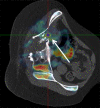

Purpose: To assess the feasibility of combined electromagnetic device tracking and computed tomography (CT)/ultrasonography (US)/fluorine 18 fluorodeoxyglucose (FDG) positron emission tomography (PET) fusion for real-time feedback during percutaneous and intraoperative biopsies and hepatic radiofrequency (RF) ablation.

Materials and methods: In this HIPAA-compliant, institutional review board-approved prospective study with written informed consent, 25 patients (17 men, eight women) underwent 33 percutaneous and three intraoperative biopsies of 36 FDG-avid targets between November 2007 and August 2010. One patient underwent biopsy and RF ablation of an FDG-avid hepatic focus. Targets demonstrated heterogeneous FDG uptake or were not well seen or were totally inapparent at conventional imaging. Preprocedural FDG PET scans were rigidly registered through a semiautomatic method to intraprocedural CT scans. Coaxial biopsy needle introducer tips and RF ablation electrode guider needle tips containing electromagnetic sensor coils were spatially tracked through an electromagnetic field generator. Real-time US scans were registered through a fiducial-based method, allowing US scans to be fused with intraprocedural CT and preacquired FDG PET scans. A visual display of US/CT image fusion with overlaid coregistered FDG PET targets was used for guidance; navigation software enabled real-time biopsy needle and needle electrode navigation and feedback.

Results: Successful fusion of real-time US to coregistered CT and FDG PET scans was achieved in all patients. Thirty-one of 36 biopsies were diagnostic (malignancy in 18 cases, benign processes in 13 cases). RF ablation resulted in resolution of targeted FDG avidity, with no local treatment failure during short follow-up (56 days).

Conclusion: Combined electromagnetic device tracking and image fusion with real-time feedback may facilitate biopsies and ablations of focal FDG PET abnormalities that would be challenging with conventional image guidance.